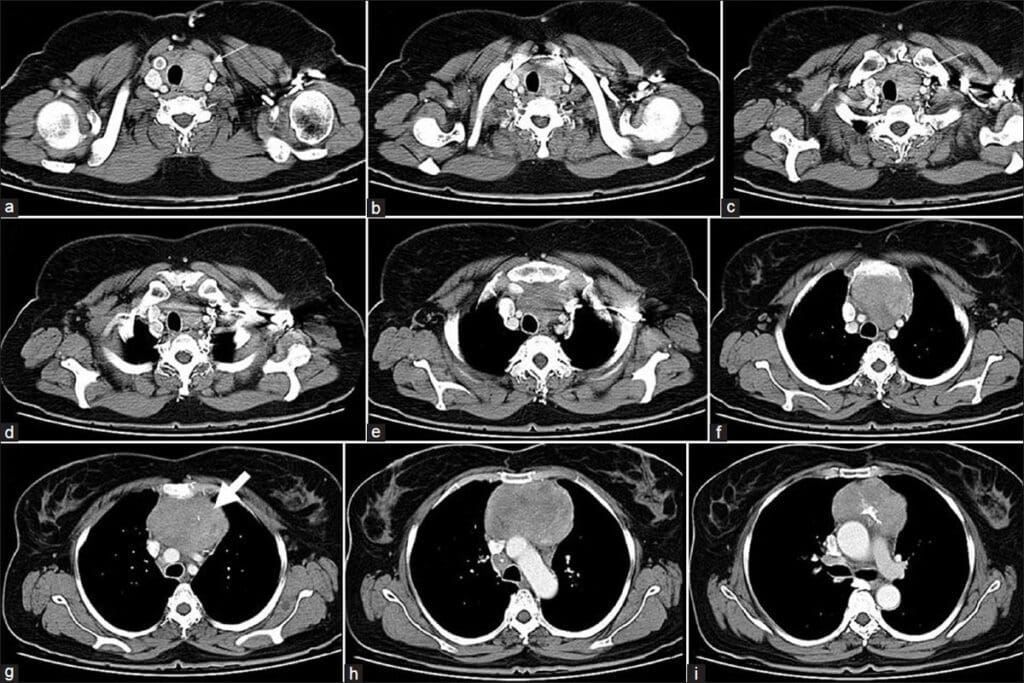

Acute Pyelonephritis

Acute pyelonephritis is an infection in the kidney, usually from bacteria. On CT urograms, it shows as renal enlargement with patchy or striated nephrograms. You might also see perinephric stranding, which means inflammation spreading beyond the kidney.

Emphysematous Pyelonephritis

Emphysematous pyelonephritis is a severe kidney infection, common in diabetics. CT scans show gas in the renal parenchyma and sometimes in the collecting system or perinephric space. It’s a serious condition that needs quick diagnosis and treatment.

Renal and Perirenal Abscesses

Renal and perirenal abscesses are pus collections in or around the kidney, caused by infections. On CT urograms, they look like low-attenuation masses with rim enhancement. Perirenal abscesses can push against or compress nearby structures.

Xanthogranulomatous Pyelonephritis

Xanthogranulomatous pyelonephritis is a long-term inflammatory kidney condition, linked to obstructive uropathy and infection. CT scans show renal enlargement, calculus, and multiple low-attenuation areas in the kidney, which are xanthogranulomatous tissues.

CT urograms are key in showing these urinary infections accurately. This helps doctors decide the best treatment, whether it’s medicine, drainage, or surgery.